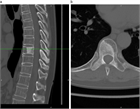

1. がんの既往のある患者が脊椎に痛みを訴えた場合、転移性脊椎腫瘍を念頭に置くことが推奨される(推奨度1)

1. 転移性脊椎腫瘍を疑った場合、全身の造影CTを撮影することが推奨される(推奨度1)

1. 転移性脊椎腫瘍と診断した場合、余命を評価することが推奨される(推奨度1)